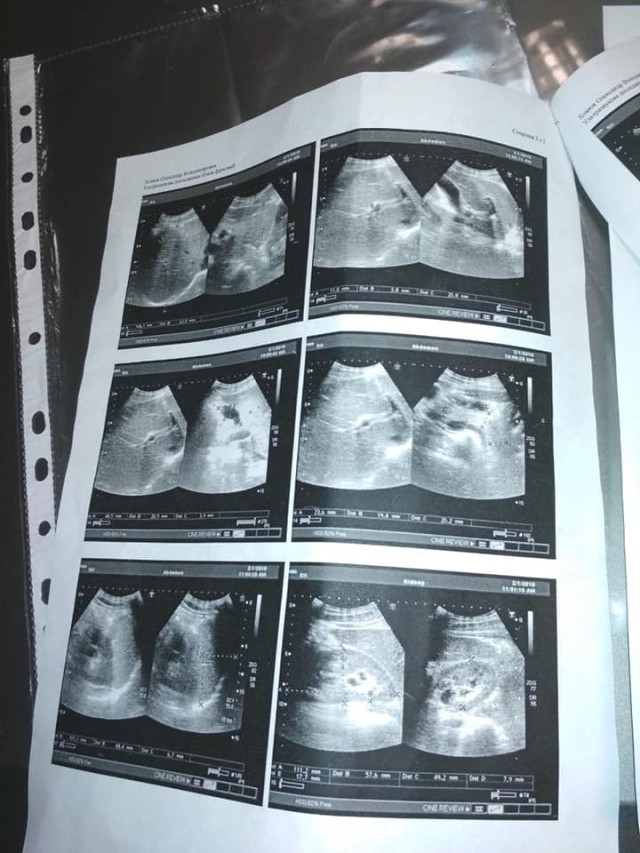

Як повідомили його близькі у Фейсбуці, у нього негоджкінська лімфома великих клітин В, початок 4 стадії.

Наприкінці листопада 2018 року росла гуля біля у пахві. Через три з половиною місяці вона збільшилась і як виявилося, це новоутвореня – злоякісна лімфома...

Як повідомили його близькі у Фейсбуці, у нього негоджкінська лімфома великих клітин В, початок 4 стадії.

Наприкінці листопада 2018 року росла гуля біля у пахві. Через три з половиною місяці вона збільшилась і як виявилося, це новоутвореня – злоякісна лімфома...